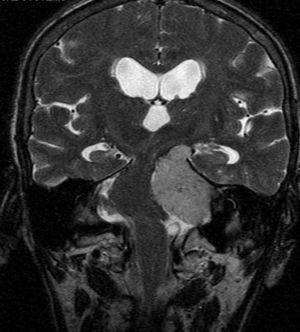

El estudio analítico mostraba hemoglobina de 11g/dl, siendo el resto de hemograma, hemostasia y bioquímica (renal, hepática y lipídica) normal. Ferrocinética, folato, vitamina B12, marcadores tumorales (CA 15.3, CA 19.9, CA 125, CEA, β2-microglobulina), proteinograma, velocidad de sedimentación globular, hormonas tiroideas, autoinmunidad (ANA, ANCA, FR, antitransglutaminasa), serologías (VHB, VHC, VIH, lúes) fueron negativos/normales. La radiografía de tórax y la TC de cuello-tórax-abdomen-pelvis no mostraron hallazgos relevantes salvo hallazgos degenerativos óseos. El electrocardiograma y el ecocardiograma mostraban estenosis aórtica e hipertrofia ventricular izquierda concéntrica, ambas con carácter leve como único dato destacable. Los estudios endoscópicos alto y bajo, así como en tránsito intestinal solo revelaron una pequeña hernia de hiato. La RM de cráneo con gadolinio (fig. 1) resultó diagnóstica al resaltar una lesión en el ángulo pontocerebeloso izquierdo extraaxial homogénea de 2,5×4×4,4cm que se introducía en el seno cavernoso, desplazando y comprimiendo el tronco del encéfalo, apreciándose del mismo modo hidrocefalia obstructiva de carácter leve. Ante estos hallazgos, y dada la situación basal de la paciente, se propone para exéresis quirúrgica donde se confirmó histopatológicamente el diagnóstico de meningioma.